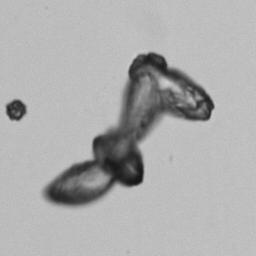

Uric acid - Irregular

Uric acid crystals occur with increased uric acid excretion or in acidic urine (pH < 5.8). Uric acid is a waste product of purine metabolism; purines are chemical compounds such as adenine and guanine (DNA components), caffeine and xanthine, and are mainly found in meat (products). The crystals can take various forms: usually diamond- or diamond-shaped plates, hexagonal plates, cylindrical structures (barrels), elongated prisms, star-shaped, spherical, needle-shaped or dumbbell-shaped crystals. They are usually yellowish to brown in color and show strong, polychromatic birefringence. They may precipitate when the urine has been kept cold prior to analysis.

The yellow discoloration of the crystals in this preparation is caused by fixation with glutaraldehyde.